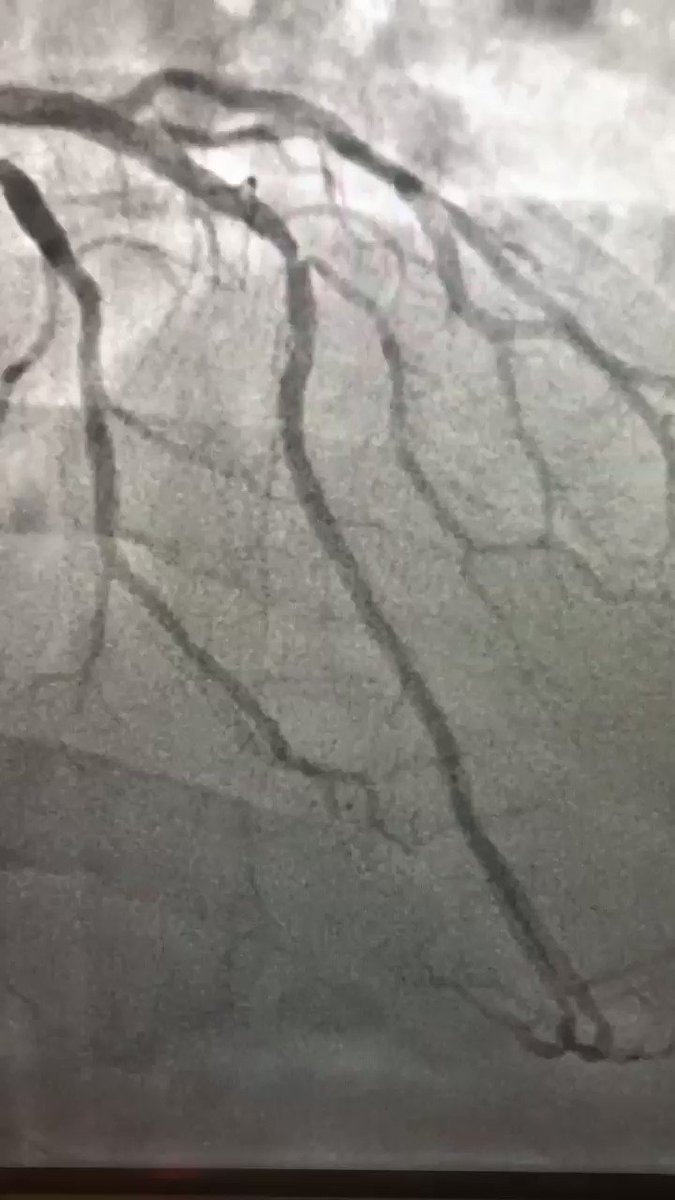

LAD proximal CTO with LM trifurcation, angiographic image View on X

LAD prox CTO LM trifurcation CABG declined

LAD proximal CTO with LM trifurcation disease

Patient declined surgical revascularization. Single transradial 8F access with EBU 3.5 guide for adequate backup. The case illustrates strategic guide selection and access planning when committing to PCI of a left main bifurcation/trifurcation in the setting of a proximal LAD CTO.

Artery: LAD prox + LM

Access: Radial 8F

Guide: EBU 3.5

Setting: CABG turndown